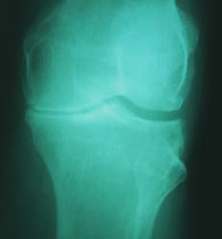

SJ is a 60-year-old male with bone on bone osteoarthritis of the left

knee. An X-ray showed arthritis of the knee (X-ray on the left). Patient started receiving

treatments at The Center For Regenerative Medicine. Today he is feeling better (X-ray

on the right).